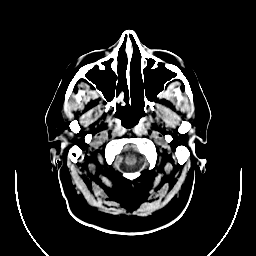

CT Study #1 -- Slice #0

[Home][Help][Clinical][Tour 1] Slice 0